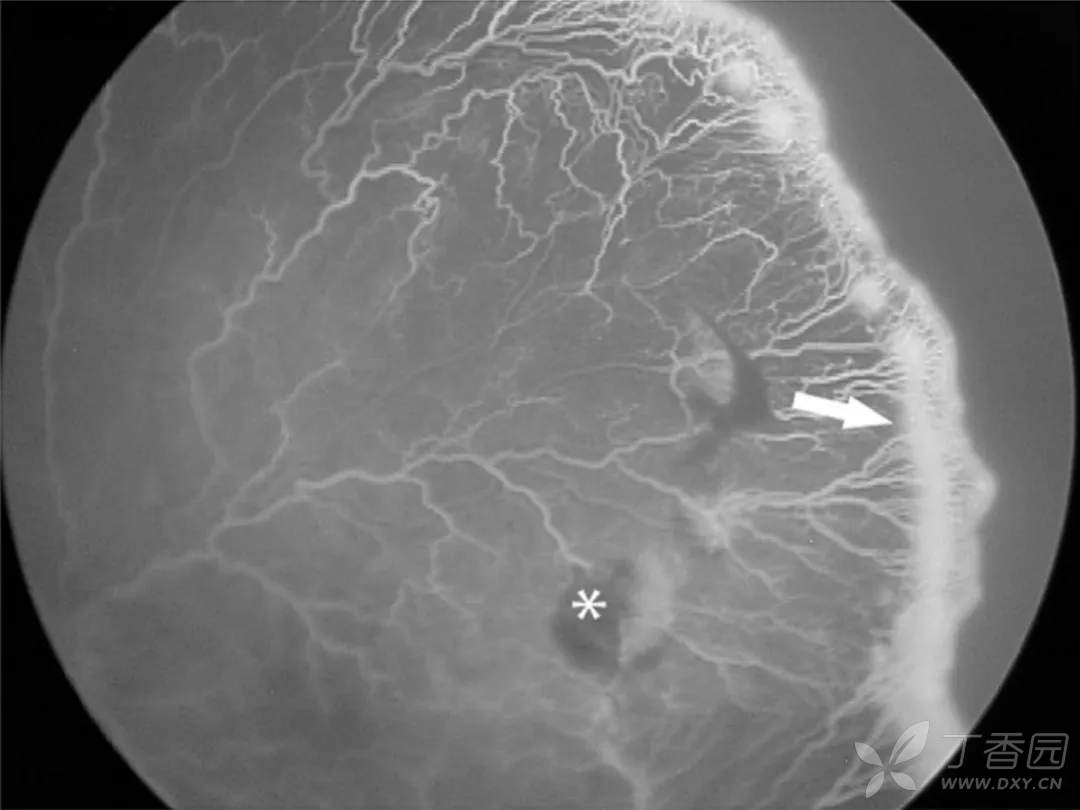

05、急进型早产儿视网膜病变

图. I区视网膜血管和无血管区边界不清(白箭),伴严重的plus病变,FFA可见明显的血管闭塞和毛细血管无灌注。